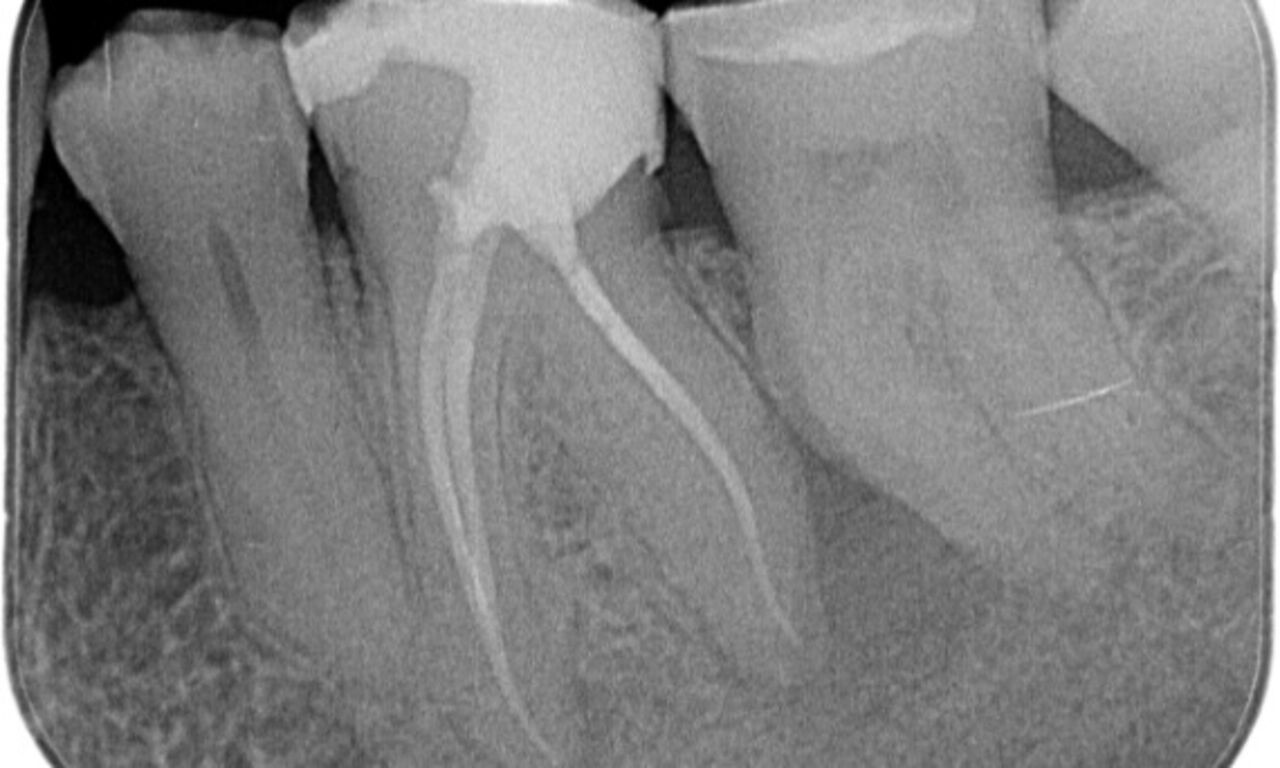

After

Access cavity was done as conservative as possible. TruNatomy was the system of choice due to the young patient’s age. We needed to preserve dentine as much as possible to increase the tooth ability to overcome occlusal load and increase the longevity of the final restoration.